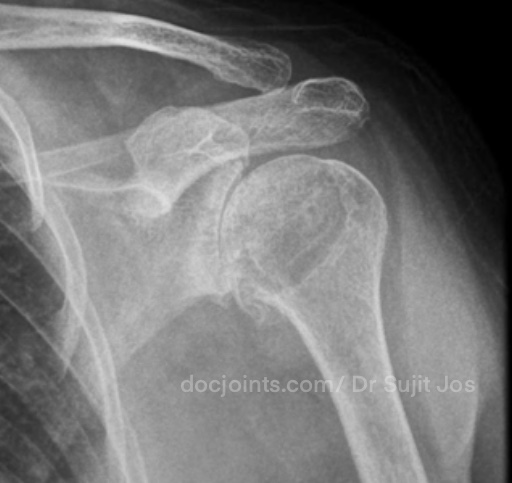

On presentation to the OP, the lifting power of the shoulder was significantly affected on strength testing (emply can test indicating supraspinatus tendon tear) and outward rotation was very weak (indicating Infraspinatus tendon tear). Xray and MRI images attached below.

There was significant fatty infiltration of the rotator cuff muscles along with osteoarthritis of the shoulder joint. Treatment options were discussed. Reverse shoulder arthroplasty is the modern treatment for this type of pathology, which can restore muscle function by orienting the shoulder centre of rotation in such a way that the Deltoid muscle can help in elevating the limb from neutral position (Read more about Reverse shoulder replacement >>).